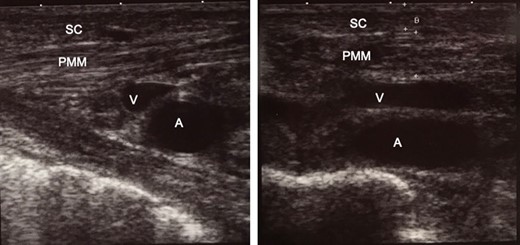

Intra-operative ultrasound examination for confirming the position of organs before infusion of tumescent local analgesia solution. The thickness of the subcutaneous tissue, 2.6 mm; and pectoralis major muscle, 5.6 mm. (a) The right side of the picture is the superior (head) side of the patient. (b) The right side of the picture is the right side of the patient. SC, subcutaneous tissue; PMM, pectoralis major muscle; V, axillary vein; A, axillary artery.